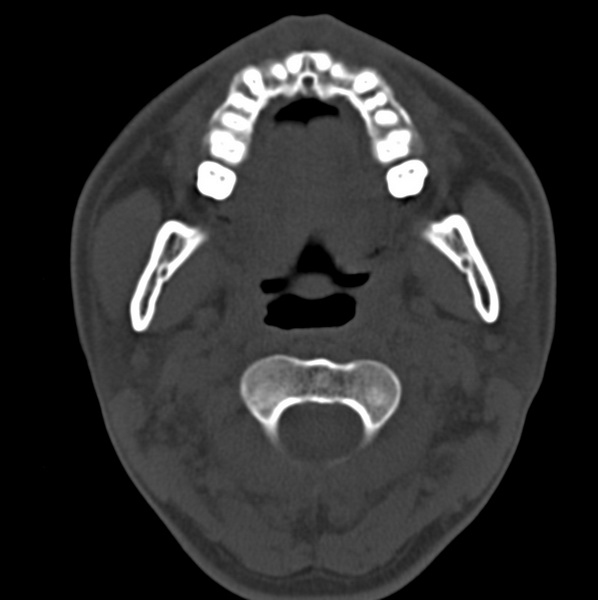

男、31、鼻咽部肿瘤放疗后请帮忙看看。

效果好,右侧破裂孔扩大,局部骨质缺损,为颅底骨质破坏。

1)鼻咽部肿瘤侵犯颅底放疗术后改变。2)左侧蝶窦炎。

咽后壁增厚,左侧咽鼓管隆突增大、咽鼓管咽口变浅,同侧咽旁间隙较窄。右侧颅底骨质破坏?为什么不在同一侧?

鼻咽部肿瘤侵犯颅底放疗术后改变.